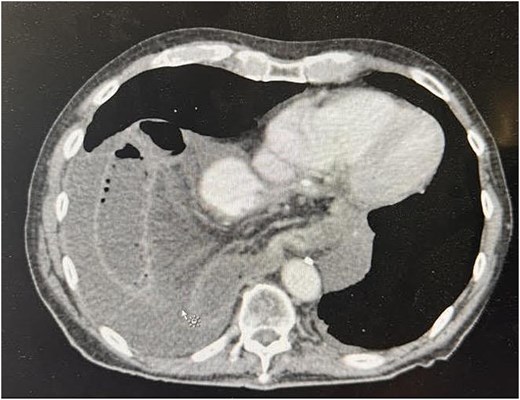

Post-op follow-up and management

The patient’s postoperative course was relatively uncomplicated. He returned to bowel function on postoperative day 2. A superficial surgical site infection was managed with local wound care. Imaging obtained 2 months after surgery demonstrated no recurrence of the hernia (Fig. 3).